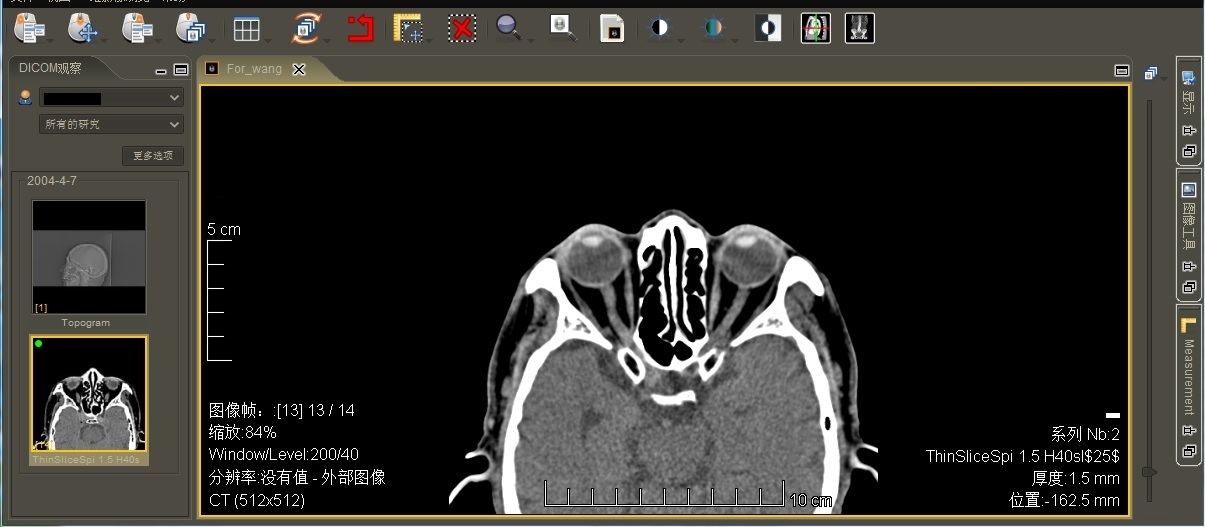

4.影像处理 支持DICOM3.0标准,可进行调节窗宽窗位、缩放、测距、旋转、明度调整,图像漫游等DICOM图像处理功能。

5.预存的图库 有头颈、胸部、腹部、脊柱、四肢等部位的不同病例的10000余幅图像。